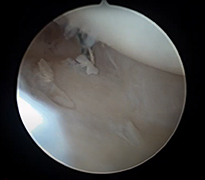

El bileği artroskopisi, el bileği ekleminin küçük kesilerden girilerek kamera ve özel cerrahi aletler yardımıyla değerlendirilmesi ve tedavi edilmesini sağlayan modern bir yöntemdir. Bu teknik sayesinde eklem içi yapılar detaylı şekilde görüntülenebilir. Özellikle bağ yaralanmaları, kıkırdak hasarları, TFCC (üçgen fibrokartilaj kompleks) lezyonları ve bazı kırık sonrası problemlerinin tanı ve tedavisinde kullanılır. Hastalar genellikle el bileğinde ağrı, hareket kısıtlılığı veya tıklama hissi ile başvurur.

Artroskopik yöntem, açık cerrahiye göre daha küçük kesilerle yapıldığı için doku hasarı daha azdır ve iyileşme süreci genellikle daha hızlıdır. İşlem sırasında hem tanı konulabilir hem de gerekli onarımlar aynı seansta gerçekleştirilebilir. Ameliyat sonrası kısa süreli istirahat ve ardından kontrollü egzersiz programı önerilir. Uygun hastalarda el bileği artroskopisi, ağrının azaltılması ve fonksiyonun geri kazanılması açısından etkili ve güvenilir bir tedavi seçeneğidir.